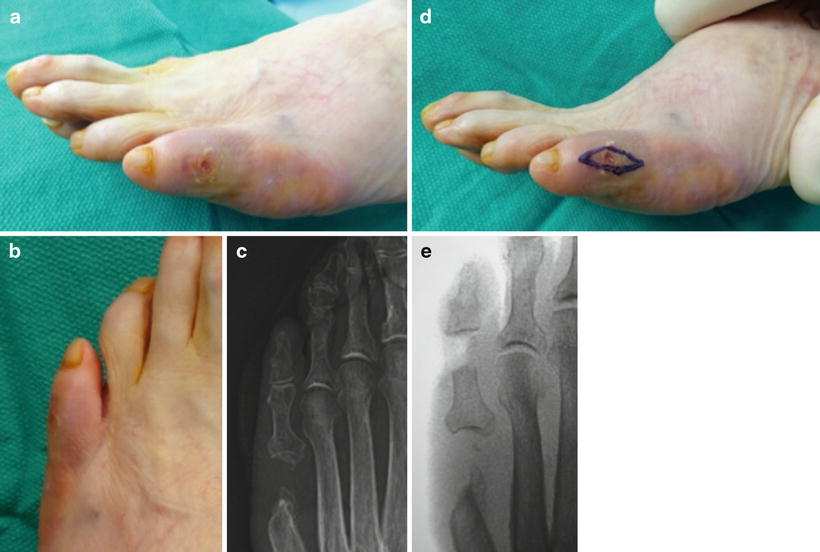

Figure 2 from Distal Syme Hallux Amputation for Tip of Toe Wounds and Toenail Excision Icd 10 Use 11730 for 'avulsion' of the ingrown nail and nail plate for temporary removal. Based on comments that cpt® code 11750 includes excision of nail and nail matrix, partial or complete and therefore another area. Wedge excision, wedge segmental excision, or. Surgical procedures for ingrown nails include the following: Icd 10 code for unspecified open wound of unspecified toe(s) with. Toenail Excision Icd 10.

a) patient with ingrown toenail; b) Vshaped excision in the angle of Toenail Excision Icd 10 Cpt code 11765 requires an excision of a wedge of the skin of the nail fold from the involved side of the toe. Wedge excision, wedge segmental excision, or. Based on comments that cpt® code 11750 includes excision of nail and nail matrix, partial or complete and therefore another area. It is found in the 2025 version of the. Partial. Toenail Excision Icd 10.